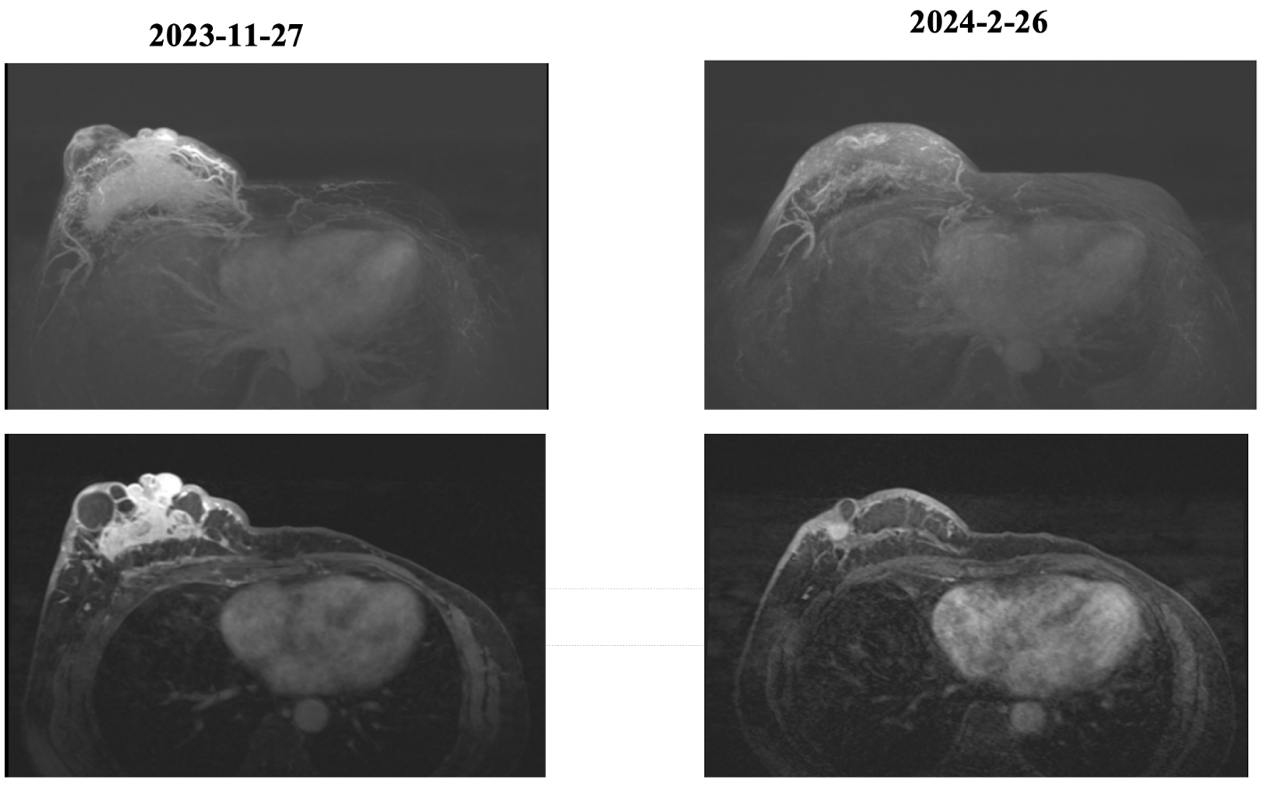

MR乳腺平扫+增强组合(3.0T):征象描述:右乳腺见不规则团片状混合信号,实性成分呈等T1稍长T2信号,DWI呈高信号,ADC呈低信号,并见多发大小不等的囊性长T1长T2信号,局部见少许短T1稍短T2出血信号,病灶边界不清,范围约56mm×91mm×74mm,增强扫描病灶实性部分明显不均匀强化,动态增强曲线呈流出型,病灶血管丰富紫乱,向前累及乳头导管及Cooper韧带,皮肤增厚、凹陷,向后局部紧贴胸壁肌层。左乳腺术后缺如。右侧腋下见数枚增大淋巴结,较大者短径约12mm,边界清楚,信号及强化均匀。

诊断意见:

右乳腺不规则肿块伴多发囊变、少量出血,符合乳腺癌,BI—RADS6类.2.右侧腋下增大淋巴结,考虑淋巴结转移可能。

治疗方案:HR+/HER2-乳腺癌晚期一线治疗:经过MDT讨论,该患者制定治疗方案为:瑞波西利600mg qd+戈舍瑞林3.6mg/28天+阿那曲唑1mg qd

疗效评估:PR

本次治疗后的转归及后续策略:患者治疗期间规律在北京大学深圳医院随访复查,主管医生应用本院创新型的院后管理服务平台随访追踪:用于肿瘤疗效评估的影像学检查、肿瘤标志物的变化,血常规、肝功能、心电图等医生关注的不良反应监测指标均可在手机小程序可视化展现,并与患者进行线上沟通。截止发稿日期,该患者仍在当前治疗方案随访中,肿瘤在治疗前3个月快速退缩,疗效评估为PR,此后维持SD状态,PFS已达20个月。

2023年底因“发现右侧乳腺肿物6年余,增大3月余”入院,诊断为右侧乳腺浸润性癌伴右侧腋窝淋巴结、右侧锁骨上淋巴结、左侧胸骨旁淋巴结转移。患侧双侧乳腺癌的分型均为HR+/HER2-。左侧乳腺癌术后未规律治疗,并且在3年后出现右侧乳腺癌,难以判断是左侧乳腺癌转移至右侧,亦或是右侧异时新发的乳腺癌进展至左侧胸骨旁淋巴结,但这并不影响患者此时为晚期乳腺癌的诊断:右侧乳腺浸润性癌(cT4N3M1 IV 期,HR+/HER2-)。鉴于瑞波西利于HR+HER2-乳腺癌晚期一线治疗带来良好无进展生存(PFS)及生活质量获益,且唯一在晚期一线治疗阶段拥有OS获益,同时患者仍为绝经前状态,此前因对化疗作用的疑虑而拒绝放化疗,综合考虑以上因素,我们为患者制定了个性化的靶向联合内分泌治疗方案(瑞波西利600mg qd+戈舍瑞林3.6mg/28天+阿那曲唑1mg qd),该方案相对化疗副作用小。治疗过程中的粒细胞缺乏通过短期停药后得到缓解,无需药物减量,肝功能轻度异常,服用护肝药后缓解,整体耐受良好。